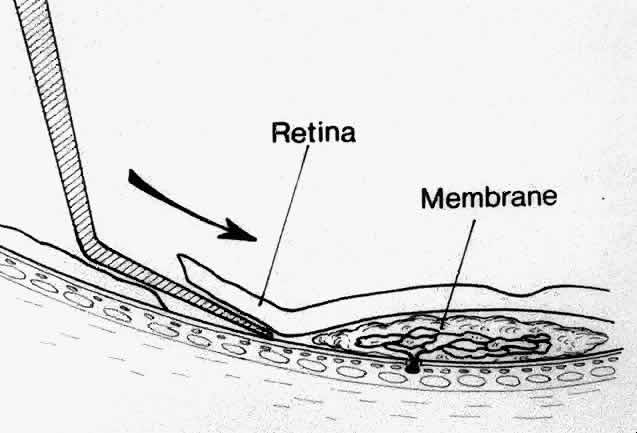

Besides being in the most advantageous location, the retinotomy should be as small as possible. Initially, we lightly diathermized the surface of the retina and then used the myringotomy blade to tease open a small hole through which an angled infusion needle was introduced.15 At the suggestion of Lambert and co-workers at Emory University, we stopped using diathermy. We now use a 120° angled, sharply pointed 36-gauge subretinal pick to pierce undiathermized neurosensory retina (Fig. 2). Occasional slight retinal hemorrhage can be controlled by transiently increasing the intraocular pressure. After the tiny hole has been made, the surgeon introduces the angled 33-gauge infusion needle beneath the retina and the assistant gently infuses balanced salt solution to elevate the neurosensory retina. This is accomplished by pushing on the plunger of a syringe that is connected to the hub of the needle by a short piece of tubing. As the fluid enters the subretinal space, attention is directed to edges of laser scars and/or adhesions to the underlying membrane (Fig. 3). Excessive infusion pressure can easily tear the retina. If areas of retina remain adherent, the infusion is stopped and the tip of an angled subretinal pick is carefully passed over the anterior surface of the membrane surface to break any residual adhesions. In a similar manner, the tip of the angled subretinal pick can be used to gently separate the thinned retina from an underlying photocoagulation scar. Occasionally, horizontal subretinal scissors are necessary to cut firm adhesions. These scissors have a similar 130° bend and blades approximately 3 mm in length to allow manipulation through an eccentric retinotomy. Trauma to foveal photoreceptors from either the pick or scissors is carefully avoided. If the retina is not mobilized over the entire photocoagulation scar, separation is achieved at least far enough into the scar to allow manipulation and extraction of the membrane without tearing the adjacent retina. The sharp tip of the angled subretinal pick is used to elevate the edge of the neovascular complex from the underlying RPE (Fig. 4). Care is taken to swing the pick in a pivoting or rotating manner to stretch or enlarge the retinotomy as little as possible. This requires close attention not only to the primary site of action at the membrane but also to the instrument shaft at the retinotomy site. In the appropriate cases, the complex dislodges easily from the underlying subfoveal RPE but remains attached to the edge of a laser scar (in recurrent cases) or to the stalk of choroidal vascular ingrowth.